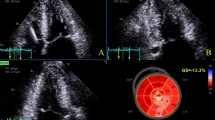

During a median follow-up of 2.8 ± 1.5 years, ten events occurred (four SCDs and six appropriate ICD shocks) for the 179 patients. In the Cox univariate analyses (Table 4), only maximal wall thickness, and mean LV LS in hypertrophic area were significantly predictive of SCD and appropriate ICD shock (p < 0.05), particularly transmural LS (HR = 0.83 [95% CI 0.72–0.95], p = 0.01). As multicolinearity between maximal wall thickness and LS in hypertrophic area was detected by a VIF test > 3.0, we did not performed any Cox multivariate analysis. Kaplan–Meier survival curves of (transmural) LS in hypertrophic area predicting SCD or appropriate ICD shock are presented in Fig. 2 (p for log-rank = 0.014). Figure 3 displays an example of a patient.